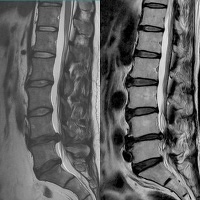

3.頚椎・腰椎の椎間板ヘルニアのチェック

当院ではGE社製の1.5T MRI装置を導入しております。

脳以外にも脊髄、関節、胸腹部(癌のチェック)、全身の血管(腹部大動脈瘤)、前立腺、子宮などの検査が可能です。できるだけ当日に検査を行うことで患者様に安心して頂くことを心がけています。診断は放射線科医師に依頼しており、適切な診断をしていただいております。検査の結果は翌日にはご連絡可能です。

腰椎椎間板ヘルニア(T2像)